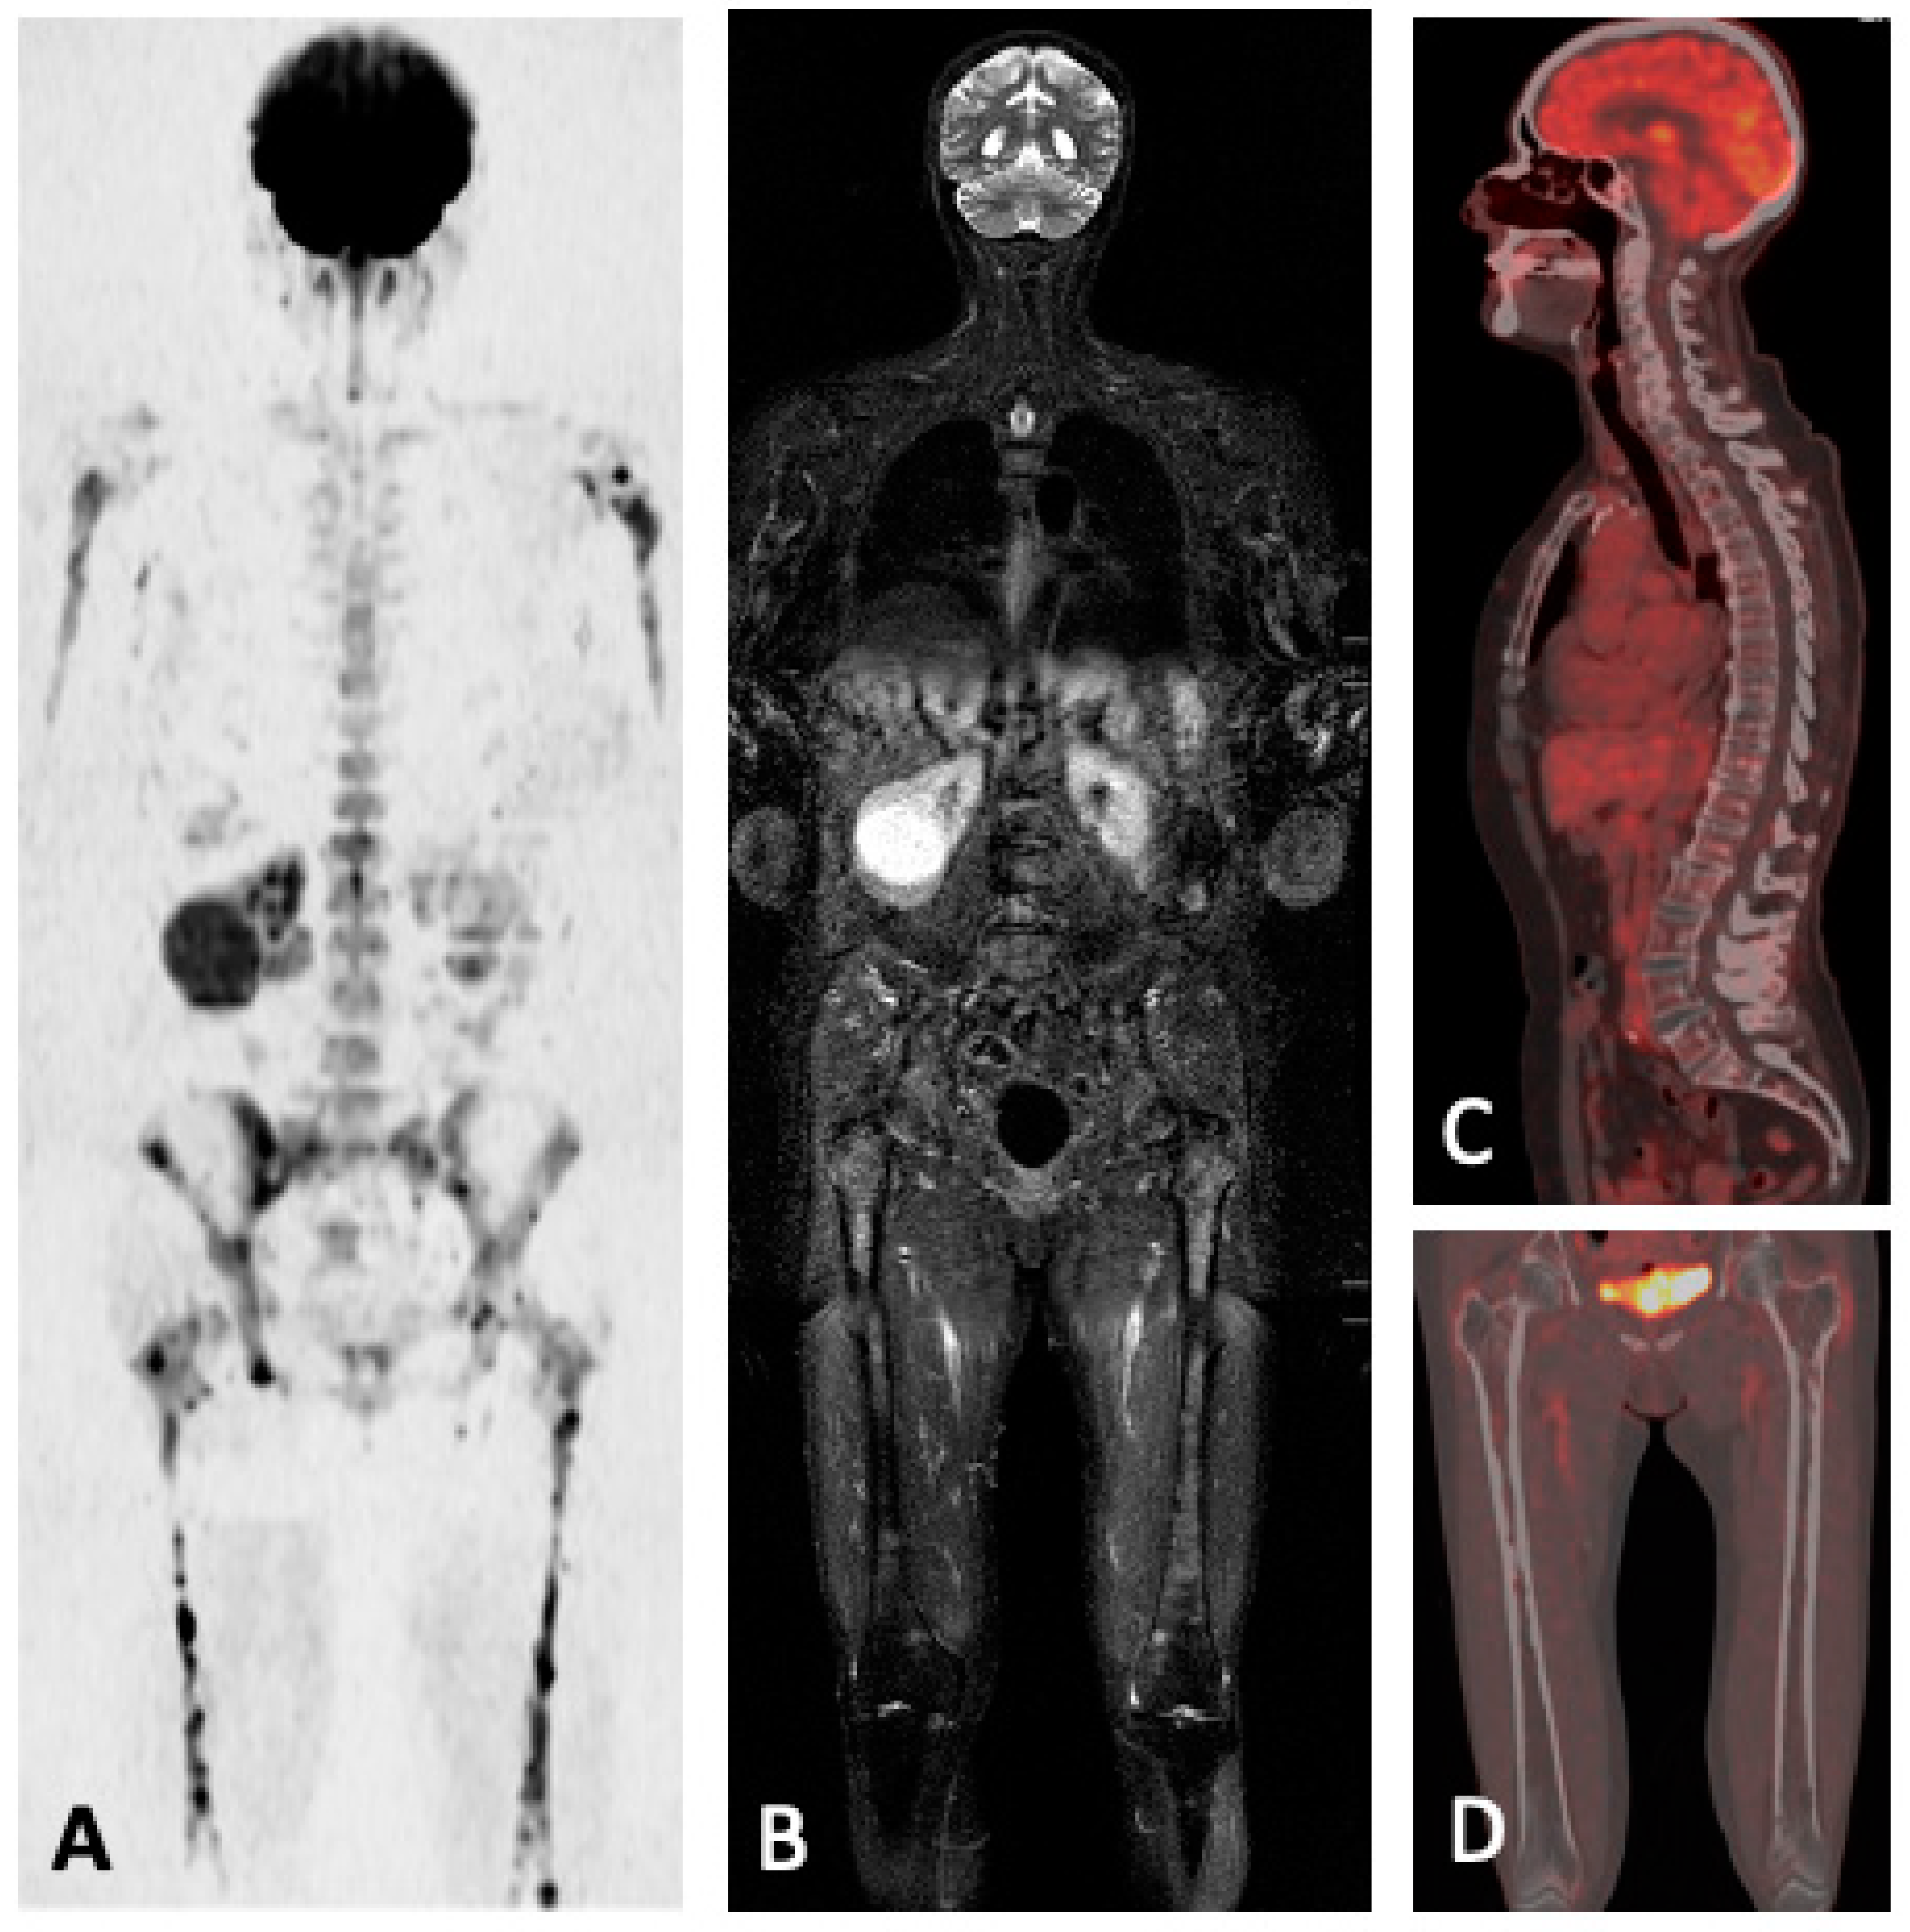

5. PET

5.1. PET/CT

5.2. FDG-PET/MRI